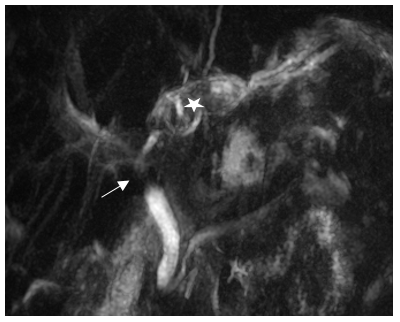

METHOD. X-RAY EXAMINATION OF THE ESOPHAGUS AND ITS SPHINCTERS AT MAXIMUM PRESSURE IN THE STOMACH

This method can be part of an X-ray examination of the esophagus, stomach, and duodenum or as an independent study if the suspicion of GERD was not confirmed after endoscopy. The patient, lying on the X-ray table, continuously drinks barium suspension through a straw from a jar standing at his head. When the barium runs out (200-250 ml), he immediately raises his straightened legs. At this moment, an x-ray is taken from the pharynx to the body of the stomach. It should be noted that a delay between the last swallow and the x-ray may necessitate a repeat examination because the x-ray will only show traces of barium in the esophagus. After the first radiograph, the subject gets up, but after 5 minutes he lies down again on the X-ray table. A second radiograph is taken at rest to determine the completeness of barium evacuation into the stomach and the possibility of free reflux (Figure 3).

Figure 3. Radiographs of patients with GERD performed at high pressure in the stomach. (a). A sharp expansion of the esophagus (3.8 cm with a norm of 1.5 cm), and a significant shortening of the LES (1.4 cm with a minimum norm of 3.2 cm). (b). The patient takes only liquid food with frequent vomiting after meals. Signs of severe esophagitis are combined with high tone of the esophagus (narrow lumen). LES is 2 cm long with the presence of folds. The proximal sphincter (PS) is 0.7 cm long. An expanded segment of the esophagus is determined between upper esophageal sphincter (UES) and aortal esophageal sphincter (AES). (c). Expansion of the esophagus and the phrenic ampulla {a}, shortening of the LES, uneven contours of the esophagus. (d). Typical functional narrowing at the level of the aortic arch in a patient with extraesophageal symptoms that disappeared after taking a 1.9 cm tablet. This is the aortic esophageal sphincter (AES) that I described, which occurs in GERD because of acid retention at the site of an anatomical narrowing of the esophagus [49]. (e). The functional proximal sphincter (PS) has contracted above the phrenic ampulla. It occurs in GERD to close the ampulla proximally. This allows pressure in the ampulla to be higher than in the stomach to expel the bolus into the stomach. The difference in the shape of the folds in the esophagus and LES (2 cm long) is due to different width and tones [50,51].

Radiometric analysis of radiographs